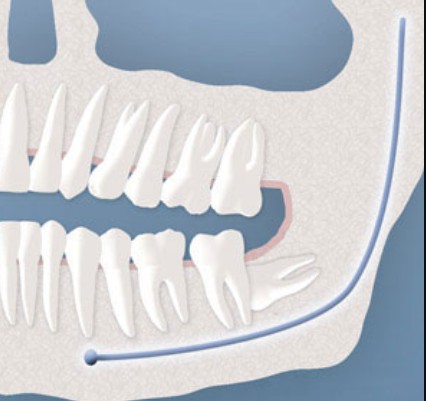

Tìm hiểu mọi điều về răng khôn mọc ngầm Răng khôn (còn gọi là răng hàm số 8 hay wisdom teeth) là chiếc răng mọc sau cùng trong hàm, thường xuất hiện ở độ tuổi ...